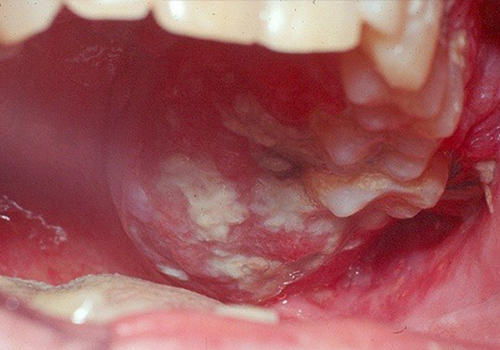

10 Hình ảnh ung thư khoang miệng qua các giai đoạn đây là một trong những loại bệnh ung thư thường gặp nhất trong các loại ung thư vùng đầu cổ. Bệnh đang ngày càng có xu hướng gia tăng ở người trẻ tuổi. Cùng xem những hình ảnh ung thư miệng qua bài viết sau để kịp thời phát hiện căn bệnh này.

Hình ảnh ung thư miệng qua các giai đoạn

Ung thư miệng là khối u ác tính, có thể xuất hiện ở bất kỳ vị trí nào trong miệng, bao gồm lưỡi, hàm, má ...

+ Miệng thay đổi màu sắc: có những vệt hoặc đốm nhỏ màu trắng, hồng.

+ Chữa lành vết loét trong miệng: Vết loét không đau, hơi cứng, sần, rối.

+ Khi bệnh tiến triển nặng, người bệnh thấy đau miệng, niêm mạc bị tổn thương, viêm loét. Chảy máu có thể xảy ra tự nhiên hoặc sau chấn thương nhẹ. Nó cũng có thể chảy máu sau khi ăn hoặc sau khi chải răng.